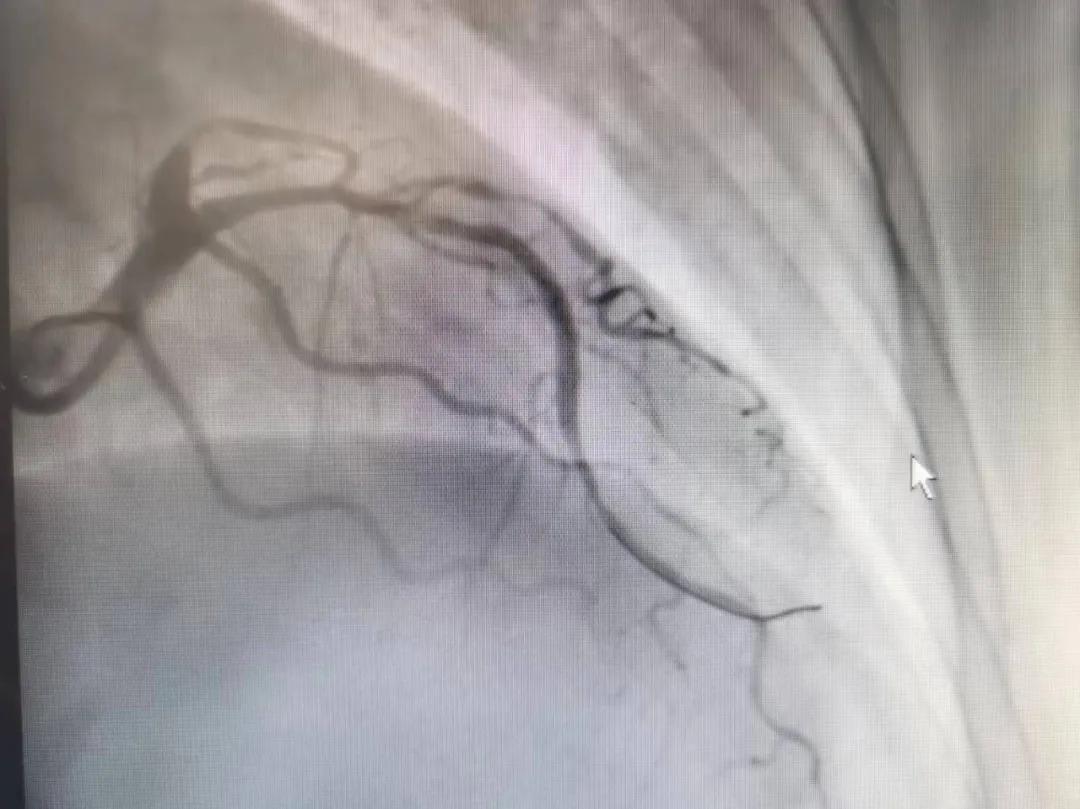

王瑾院長(zhǎng)和李慧新主任帶領(lǐng)介入團(tuán)隊(duì)充分評(píng)估,決定行前降支冠狀動(dòng)脈鈣化病變旋磨術(shù),術(shù)中應(yīng)用1.5mm旋磨頭,以15萬(wàn)-17萬(wàn)轉(zhuǎn)/分速度共對(duì)病變旋磨3次,累計(jì)旋磨時(shí)間60秒,后復(fù)查造影示鈣化明顯減輕,為后續(xù)操作創(chuàng)造了良好條件,隨后應(yīng)用預(yù)擴(kuò)張球囊、切割球囊再次處理病變,并順利植入支架1枚,復(fù)查造影顯示支架膨脹及貼壁良好,無(wú)夾層、血腫、慢血流等情況,手術(shù)順利完成?;颊咝g(shù)后無(wú)不適,胸悶、胸痛癥狀明顯緩解,順利出院。

術(shù)后